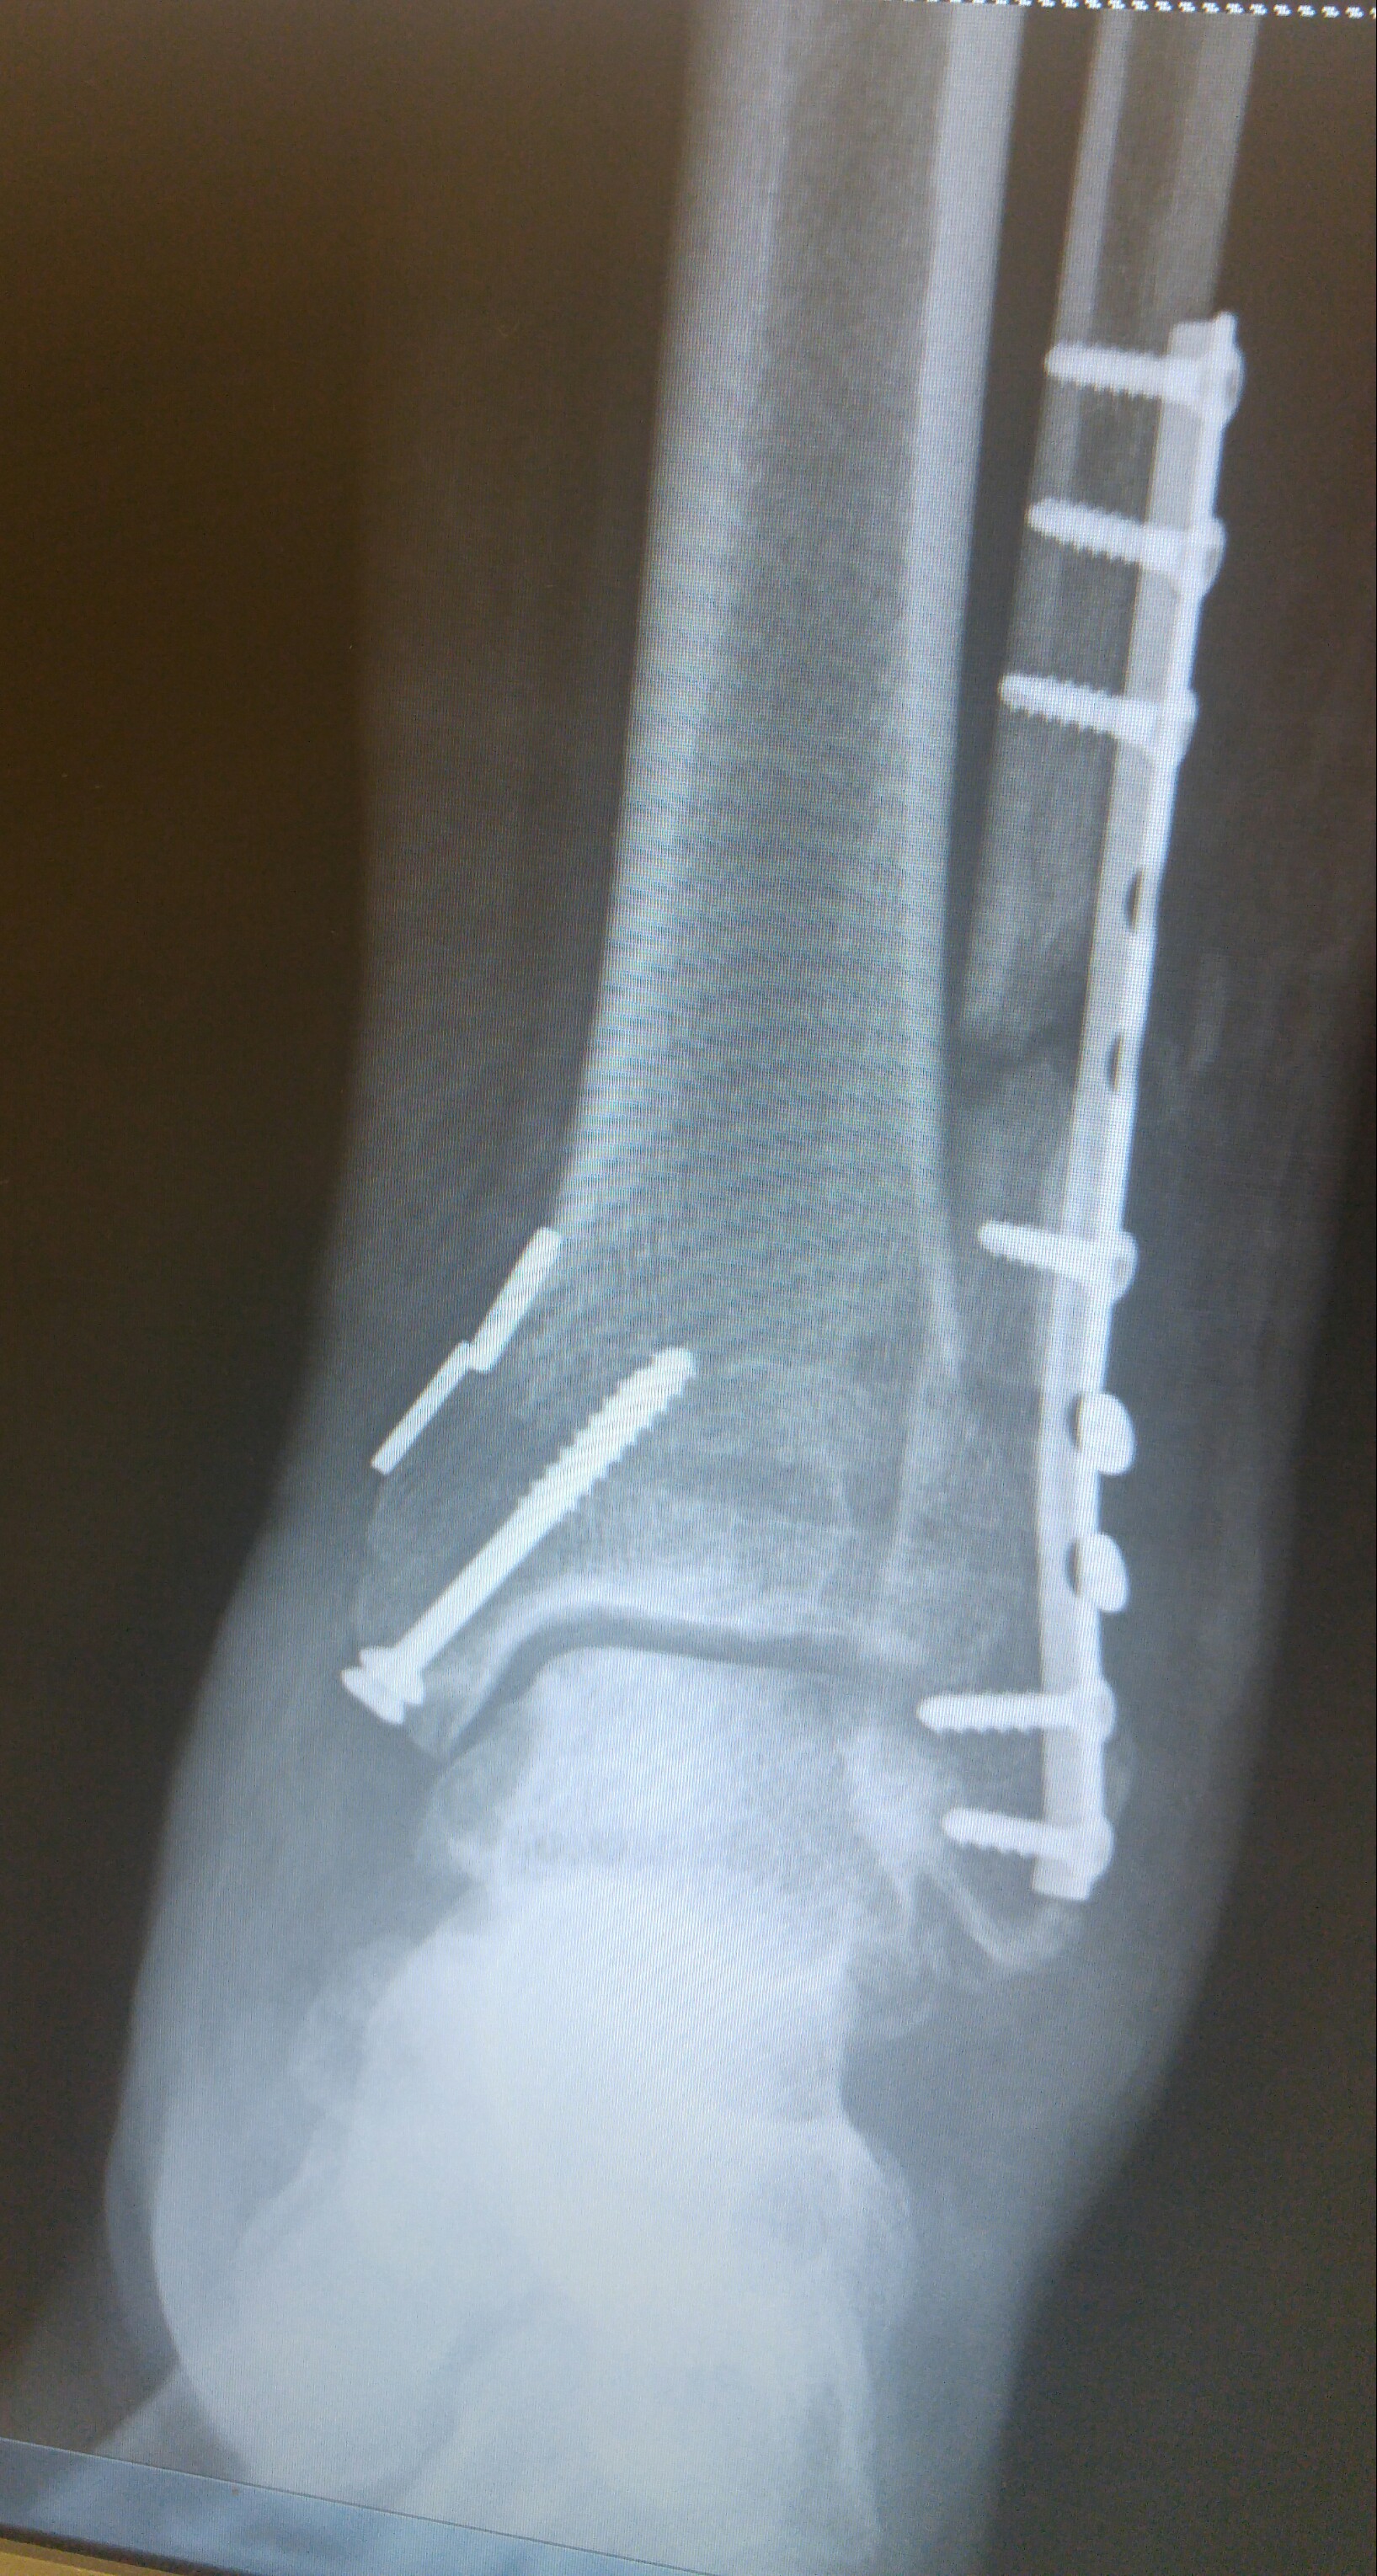

Broke my able and tore the ligament that hold the fibula and tibia in place. Did it on May 13 and here are my x-rays that were taken yesterday. Be as compliant as you can so you don't have to join the hardware club.

Due to the remaining gap in the fibula, it will be at least another 2 weeks before I can start putting any weight on it.

Thankfully, no. Just lots of screws, a plate and some heavy duty thread to secure the two bones in place until the ligaments heal. If you zoom in and look close at the bottom of my tibia and fibula, you will see two light grey horizontal lines. Those are the tunnels drilled and ran the sutures through to tie the two bones together. This technique is supposed to allow for more natural range of motion down the road.The Annoyed Man wrote:Holy cow! Did they actually fuse the ankle?mojo84 wrote:Glad you've been able to avoid surgery do far. Will pray your able heals on its own.

I shared the xrays just to encourage you to be compliant with the doc's instructions. If you do, your chances of avoiding surgery will increase. I had no choice about surgery. Hopefully you will be able to avoid the surgery.